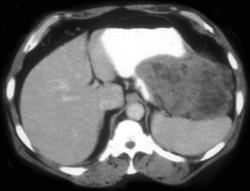

Diagnosis

Antral Carcinoma